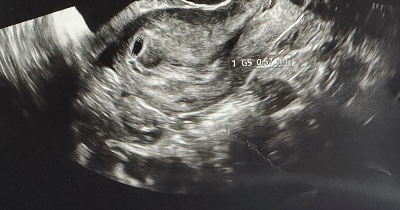

임신 7주 차에 돌입한 초기 임산부의 보건소 임산부 검사(임신초기검사) 후기를 가지고 왔습니다.

임신 7주 차에 진입한 초기 임산부입니다. 동네의 나무정원 여성병원에서 임신 확인을 받고 분만병원을 고민하다가 부모님께서 대학병원을 추천하셔서 가까운 의정부 을지대학교 병원을 다녀

| 나무정원 여성병원 야간진료 임신확인 후기(임신 확인서 발급, 비용) (37) | 2024.11.26 |